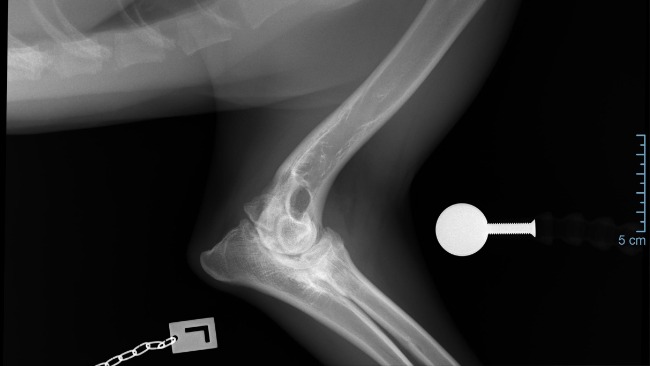

Późniejsze badanie RTG w katowickiej przychodni weterynaryjnej potwierdziło najgorsze obawy – stan łokci jest bardzo poważny, choć Axel nie wykazuje oznak bólu, co dziwi każdego specjalistę.

RTG + GT:

Łokcie – obustronnie, wyraźna inkongruencja, wyraźna podchrzęstna skleroza, cechy OA, UAP

Z weterynaryjnego na nasze: Cechy radiologiczne (Zmiany na RTG) pokazują:

OA - Artroza łokcia u psa to przewlekłe schorzenie zwyrodnieniowe stawu, prowadzące do bólu, sztywności i ograniczenia ruchu, spowodowane uszkodzeniem chrząstki i zmianami w kościach, często wynikające z dysplazji (np. niezrośnięty wyrostek dodatkowy - UAP)

• UAP: Ubytek kości podchrzęstnej w przyśrodkowej części bloczka kości ramiennej, czasem z wolnym fragmentem kostnym.

DIAGNOZA: ED – 3. Stopień

• ED (Elbow Dysplasia): Dysplazja stawu łokciowego, wada rozwojowa, która powoduje zaburzenia w budowie i funkcjonowaniu stawu.

• 3. stopień (ED 3/3): Określa najcięższą formę tej dysplazji, czyli ciężką dysplazję.